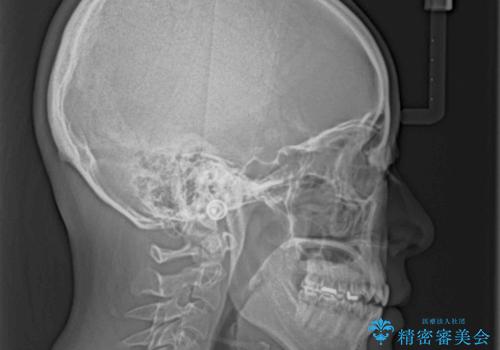

【モニター】狭い上顎歯列とオープンバイト 急速拡大装置を用いた矯正治療

- 前歯の開咬を気にして来院された患者様です。

上顎歯列が狭窄していたため、急速拡大装置により上顎骨を側方に拡大し、その後インビザラインにて矯正治療を行うこととしました。